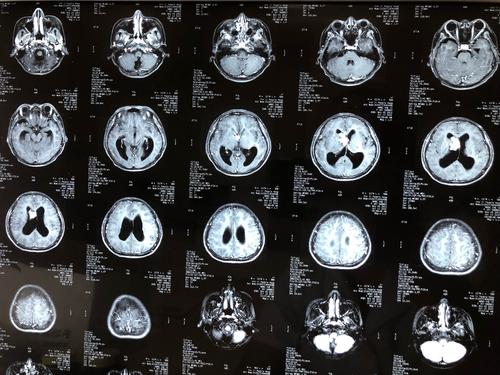

史上最全脑室解剖图谱快收藏了吧

侧脑室解剖

侧脑室ct

脑室图解

脑室系统

脑室解剖图